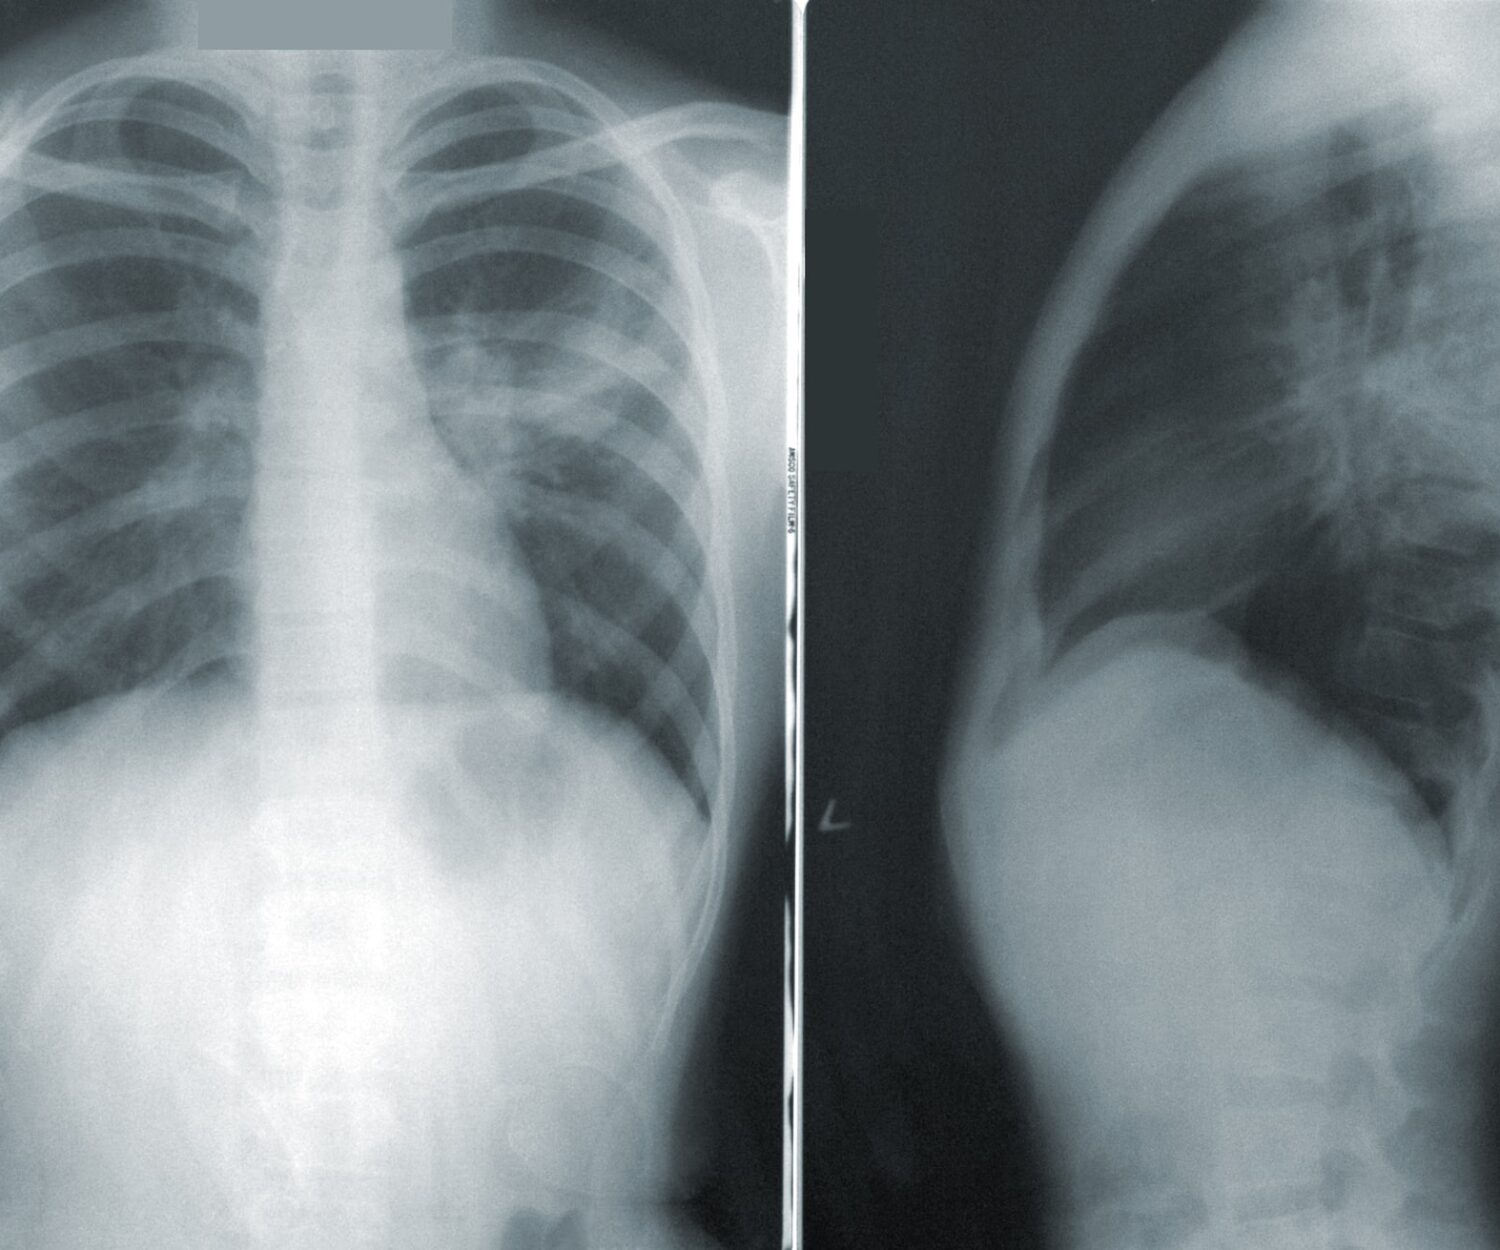

Covid 26 May 2020 ¿Puede quedar daño pulmonar? 19/04/2020 – Dr. Juan García Puig Una persona infectada con covid19, que ha llegado a un nivel avanzado de la… AdminGadea